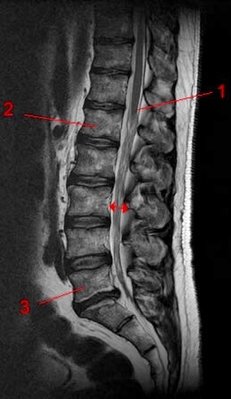

Il est écrit p5 de la ronéo 8 que L4 et L5 ont un corps vertébrale plus haut en avant qu'en arrière pour permettre le passage entre la cyphose sacrée et la lordose lombaire mais il me semble bien que c'est l'inverse, c'est plutôt un corps vertébrale plus haut en arrière qu'en avant nn ? C'est compliqué à expliquer mais quand j'utilise mon application (Skeleton) c'est clairement la partie postérieur qui est plus haute...